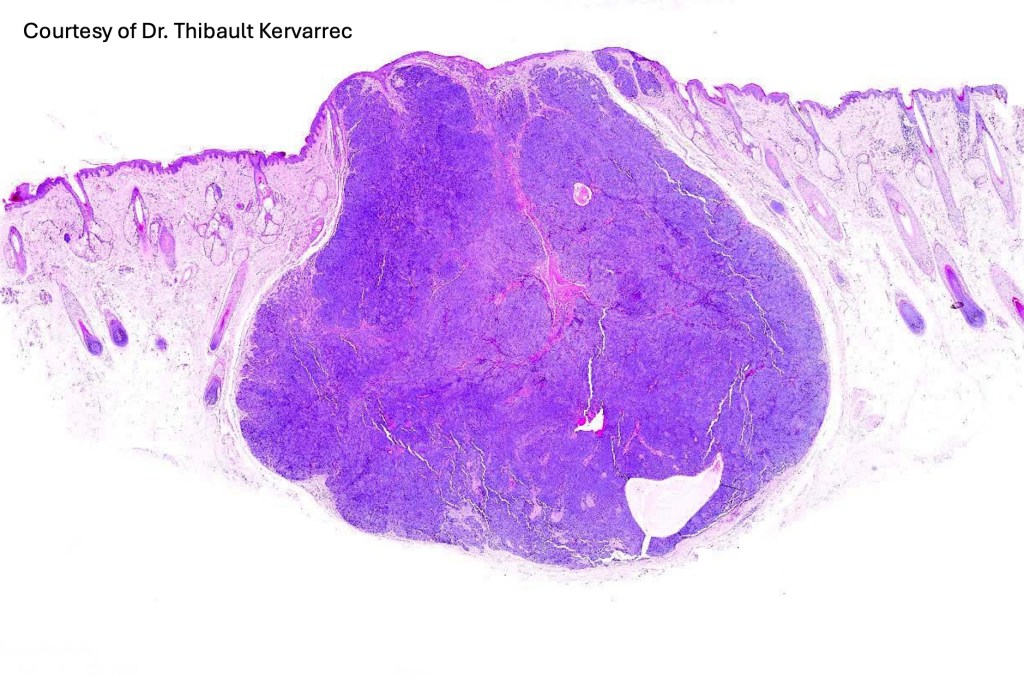

•Sharply circumscribed, unencapsulated nodule in deep dermis +/- subcutaneous fat or deeper (trichoepithelioma is much more superficial)

•Variably sized but generally large, basophilic tumor nodules composed of small uniform basaloid cells with minimal cytoplasm

•Peripheral palisading but no retraction artifact or stromal mucin deposition

•Variable keratocysts

•A rich fibromyxoid mesenchymal stroma with variable papillary mesenchymal bodies (sometimes these are absent)